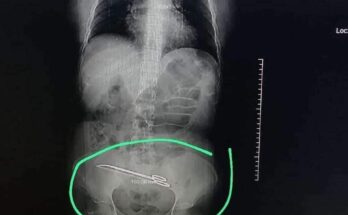

طبيب ينسى مقص داخل مريضة خضعت لعملية جراحية في طرابلس

اين الضمير اين الانسانية اين الوجدان دون حسيب او رقيب طبيب يعمل رئيس قسم التوليد في المستشفى.. دخلت المريضة مستشفى لاجراء عملية قيصرية بتاريخ ١٣/١٠/٢٠٢٢ ونتيجة الاهمال والاستهتار واللامبالاة وانعدام …